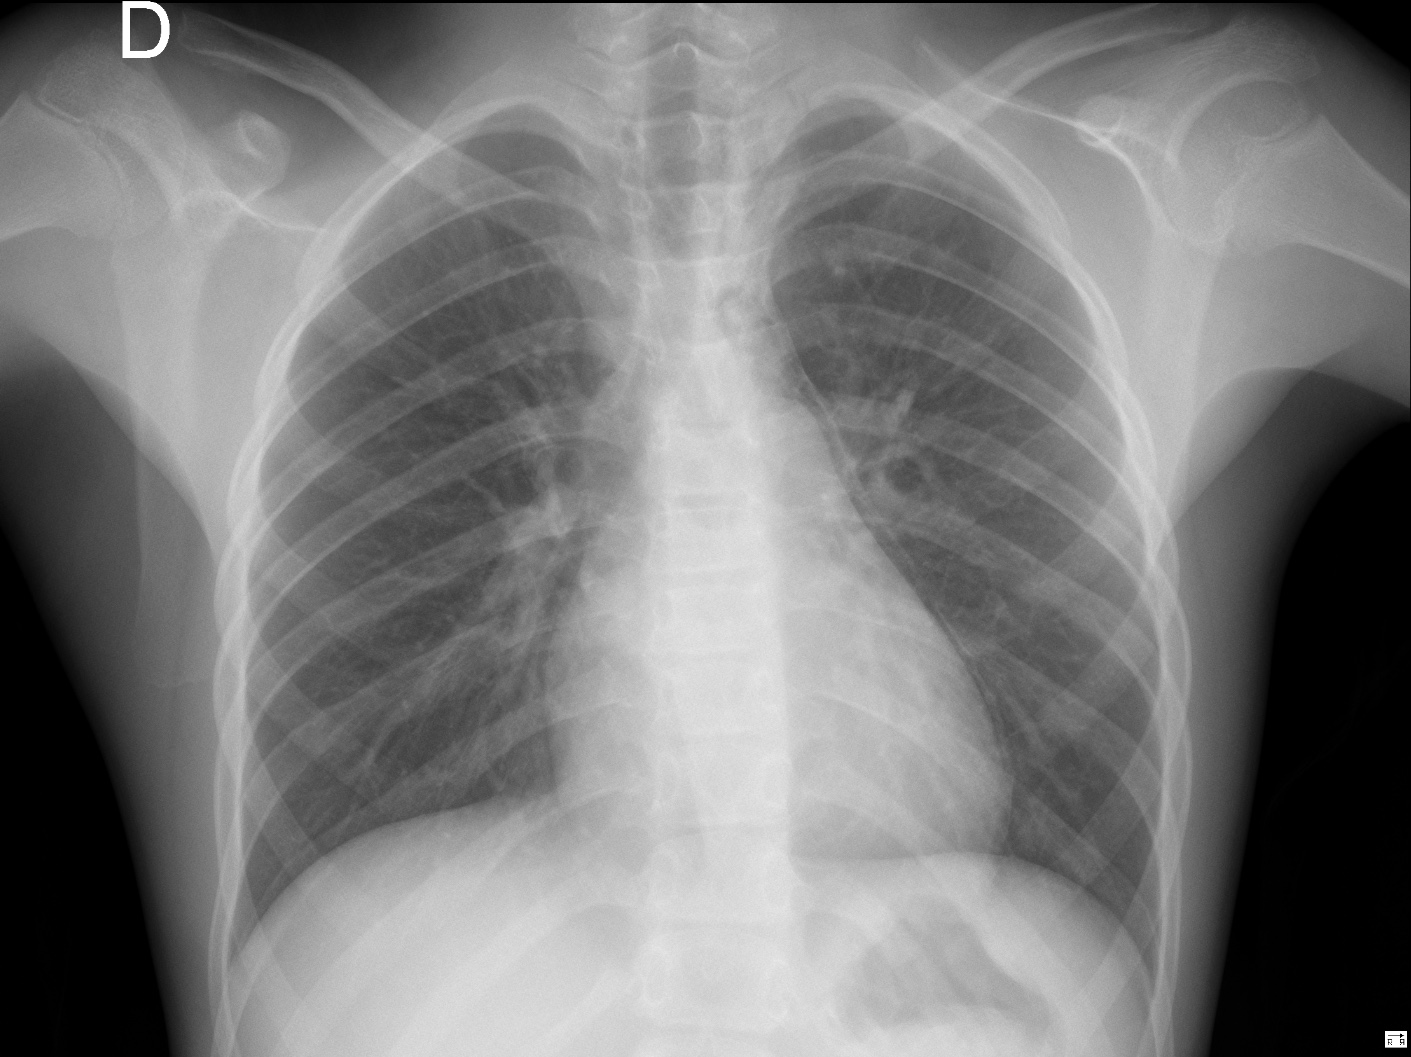

Solución: Es un estudio Normal. Silueta cardiomediastínica y parénquimas pulmonares sin alteraciones significativas.